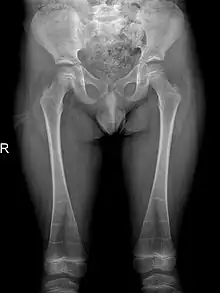

It is also reported that individuals may also have pelvic abnormalities. This includes the development of narrow iliac wings, as well as widened femoral necks. However, incidence of both symptoms are rare in patients with DSS, occurring in less than 30% of cases.[6][7]

The occurrence of DSS also leads to deformities of the limbs. 80% of patients reported with abnormalities of the metaphysis such as metaphyseal flaring, radiolucent metaphyses, abnormal metaphyseal trabeculation, which is abnormal trabecula patterns in the metaphyseal region, and epimetaphyseal sclerosis. Other limbic abnormalities include progressive bowing of long bones, which is present in rare cases.[6][7]

Sclerosis of epiphyses, diaphyses, and metaphyses with increased radiolucency are key characteristics of the disease.[18] In addition, mottled metaphyseal sclerosis and widening are also present in patients.[4][9] Development of irregular patchy sclerosis along the bone can also be identified,[9] as well as metaphyseal flaring evolve towards Erlenmeyer flask deformity with nonuniform patches of sclerosis, which are especially prevalent in older patients.[10]

The metadiaphyses, a portmanteau of the metaphysis and diaphysis,[20] are bulbous and expanded with bowing and relative radiolucency. The expanded regions are also sclerotic and gives the characteristic bone-in-bone appearance.[4]